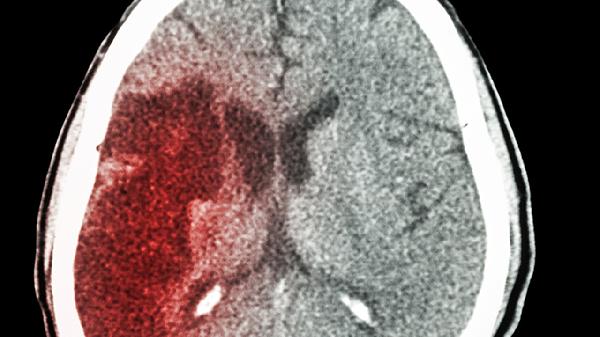

瘢痕妊娠特指胚胎植入子宫肌层瘢痕组织的异常情况,常见于既往有子宫手术史的孕妇。子宫下段剖宫产切口处肌层薄弱,局部血供异常,导致绒毛组织易侵入肌层甚至穿透子宫壁。超声检查可见妊娠囊位于子宫前壁瘢痕处,与宫腔无直接连通,周围肌层连续性中断。

早期可能无特殊症状,随妊娠进展可出现无痛性阴道流血,出血量常呈间歇性增多。部分患者伴有下腹隐痛,妊娠试验持续阳性但血HCG上升缓慢。严重者突发剧烈腹痛伴休克,提示子宫破裂可能。经阴道超声检查是诊断金标准,需观察妊娠囊与膀胱间肌层厚度。